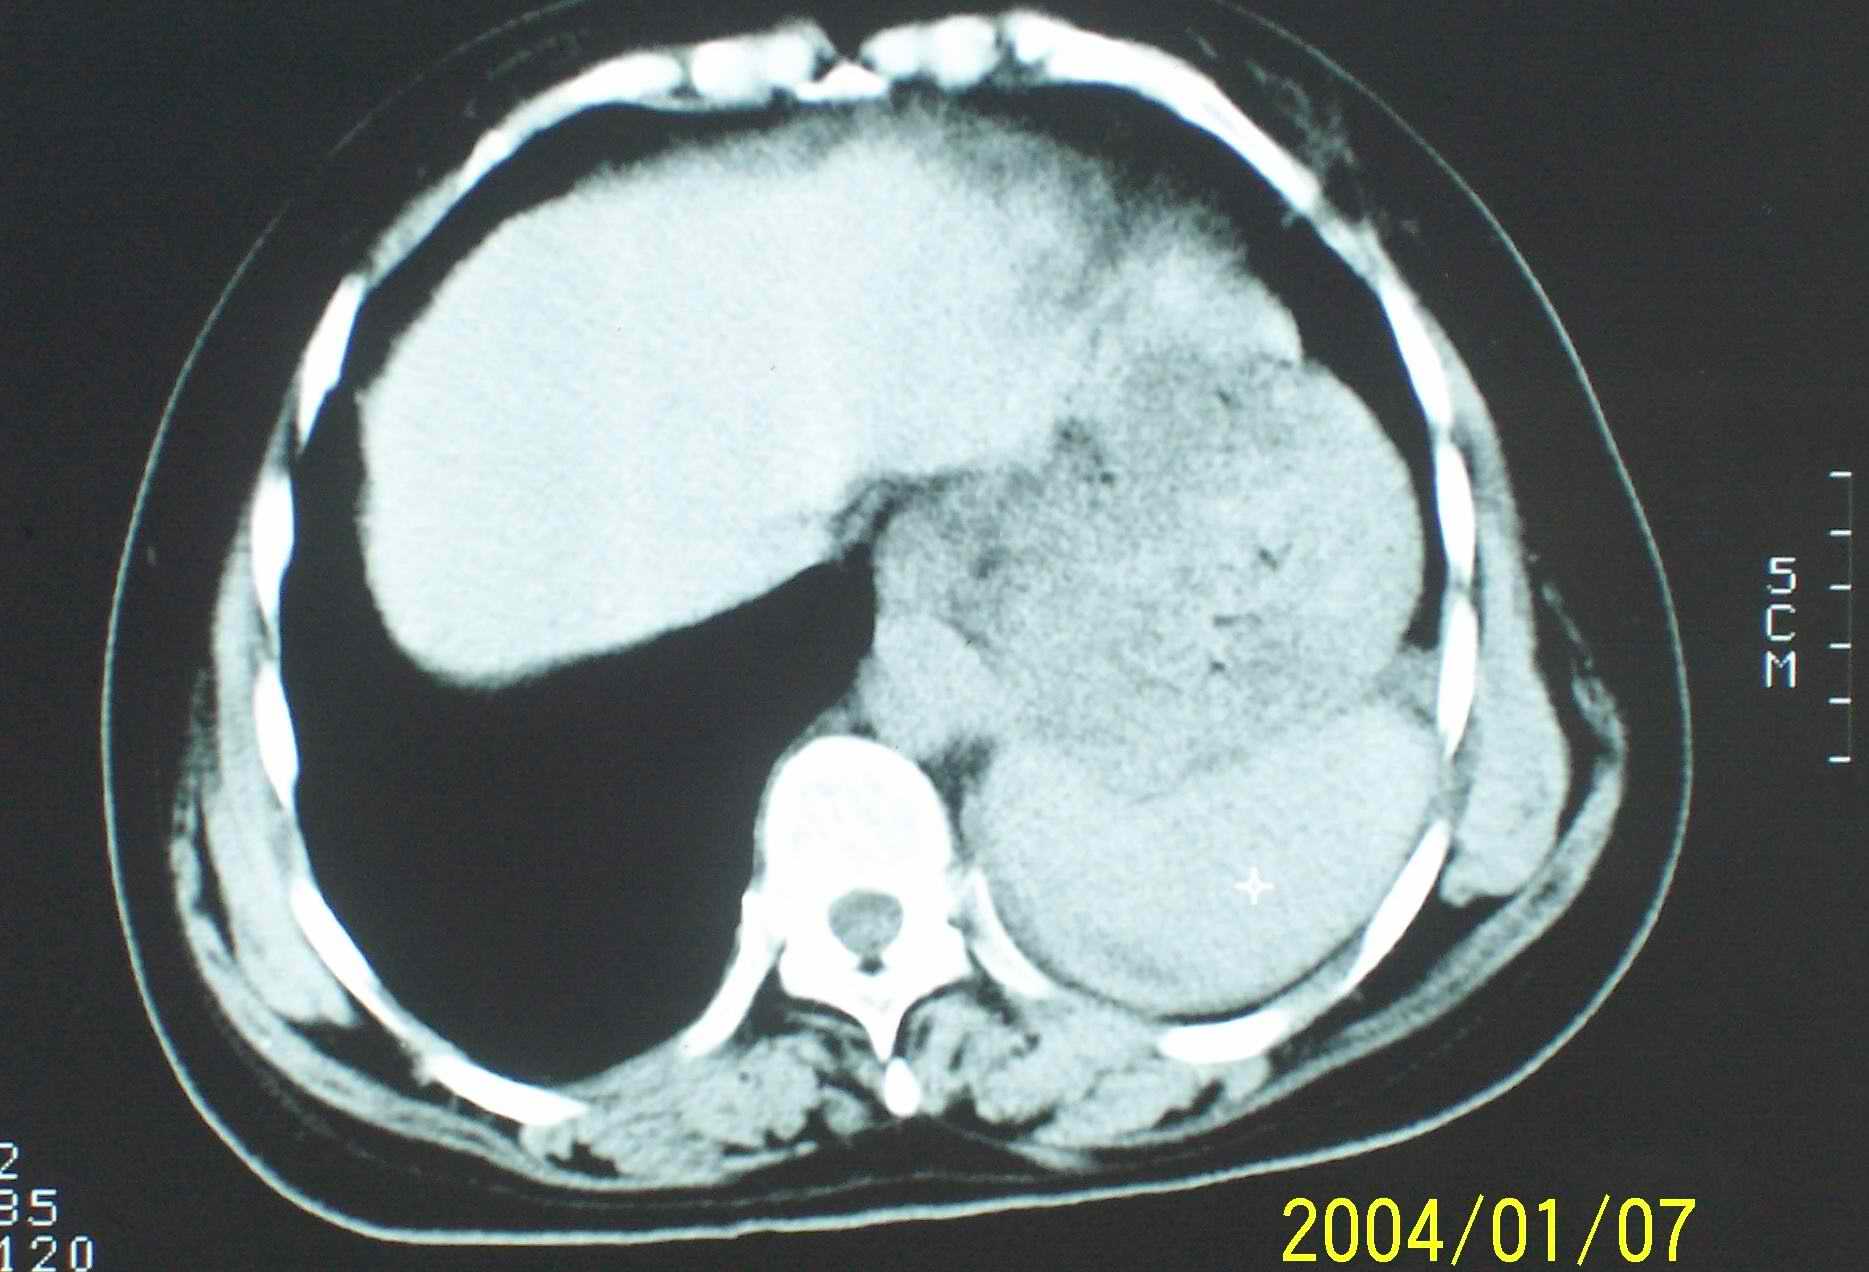

1.左侧胸腔无明显萎陷,肺体积缩小,含气量减少,纵隔心脏左移。从这个意义来讲,左下肺病灶应该首先考虑肺不张。

2.左下肺病灶密度太过均匀,边缘过于光整锐利,位置特殊,其次应该考虑隔离肺的可能。

3.连续观察不能完全否定病灶是疝入胸腔的脾脏(扫描不怎么规范,跨越过大),所以膈疝也需要考虑。

应该是脾脏,因此是膈疝,

从连续观察的层面看象是疝入的脾脏